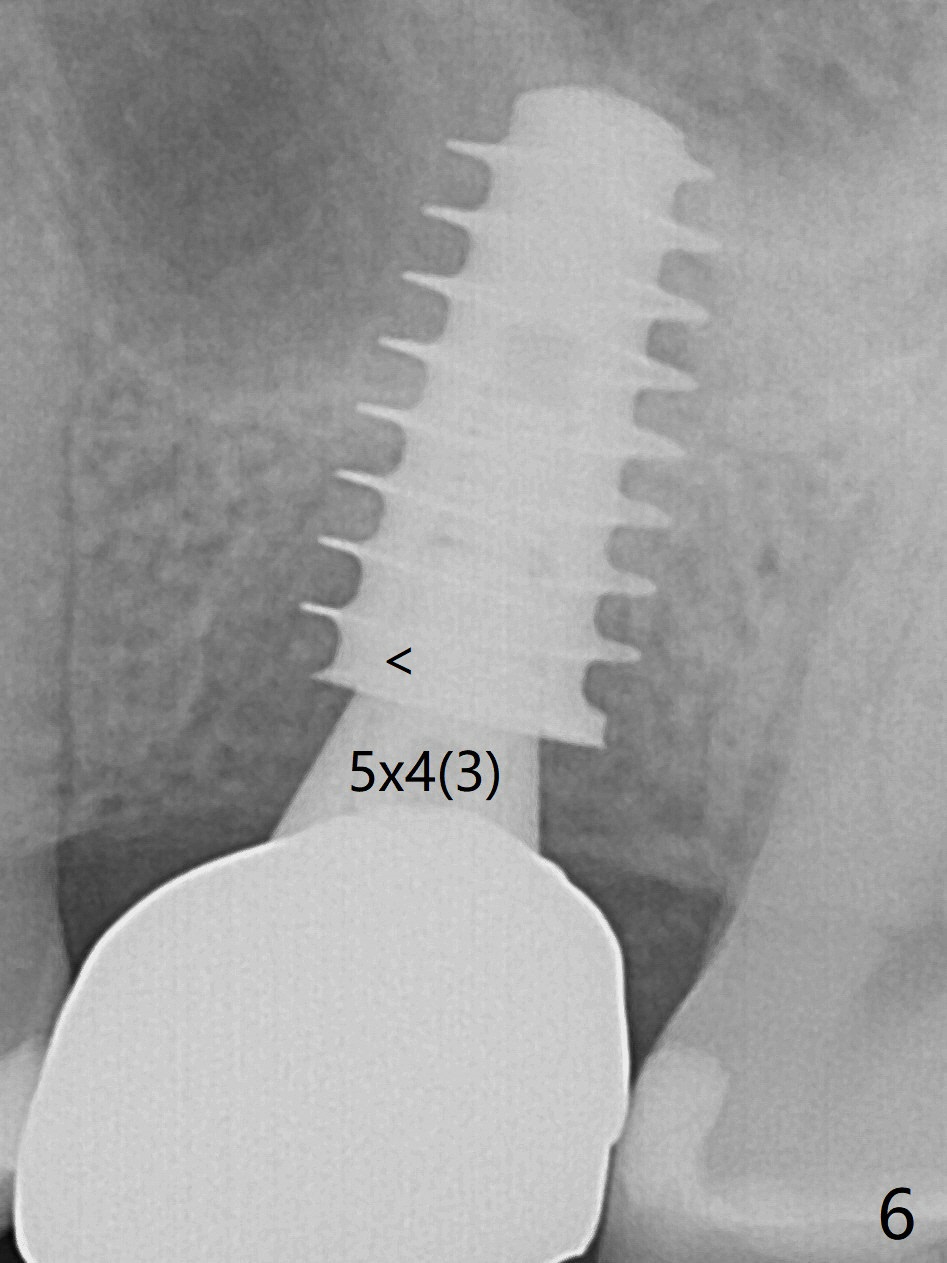

After extraction of the tooth #14 with palatal swelling (Fig.1 *), the septum (S in Fig.2) is found to be thin. Sequential osteotomy quickly deviates to the palatal socket. In spite of using Lindamann bur to remove the bone from the buccal portion of the osteotomy, the apical end of a 5x9 mm dummy implant slides into the palatal socket with the coronal end placed as buccal as possible for restoration (Fig.2 (poor trajectory)). Further use of Lindamann bur for buccal bone removal is not feasible, since the buccoapical portion of the osteotomy starts to be perforated with apparently intact sinus membrane. With insertion of Vanilla graft for sinus lift through the buccoapical portion of the osteotomy mentioned above, a 6x11 mm implant is placed with the same trajectory (Fig.2, <40 Ncm). With placement of a 6.5x4(3) mm abutment (off angle) and of Vanilla graft in the remaining sockets (Fig.2 *), periodontal dressing is applied. When the dressing is dislodged for the 2nd time (12 days postop with healing socket), an angled abutment 5x15 degree, 3 mm cuff, is placed and a provisional is fabricated. There is no sign of sinus infection. The provisional and angled abutment become loose without sinus infection 2 months postop. A 5.5x3 mm healing abutment is placed with light tenderness. If this case turns to be failure, do not stick an immediate implant from potentially infected socket into the sinus in the future. The socket appears to heal 11 months postop (Fig.4). Later a 5x4(3) mm abutment is placed for final restoration. The palatal margin is low. The abutment screw is loose <2 months post cementation, probably due to deep placement and poor trajectory (buccal). It becomes loose again 4 months later. Prior to retightening, a 6 mm profile drill is used. BW shows no bony interference (Fig.5 (opposing tooth occlusal wear; bruxism)), while PA shows the buccal bone, suggesting poor trajectory. The abutment is loose for the 3rd time 17 months post cementation. When the crown/abutment is removed, the hex is worn. After proximal reduction, the crown/abutment feels to be unable to be re-seated. When the crown is sectioned, the abutment itself is incompletely seated (Fig.7,8). The mesial crest appears to interfere with seating (Fig.8). When the 5.2x3 mm dummy abutment is seated, the buccal margin is subgingival, while the palatal one supragingival, suggesting the buccally tilted implant (guided surgery essential). A 4.5x4(4) mm pair abutment seems to be seated completely (Fig.9). The hex of the 5x4(3) mm abutment is worn, but the abutment seems to be able to be seated completely (Fig.11), although not so crisply (easily) as the unworn one clinically. Return to Upper Molar Immediate Implant, Prevent Molar Periimplantitis (Protocols, Table), Armaments Screw Xin Wei, DDS, PhD, MS 1st edition 06/26/2018, last revision 12/20/2020